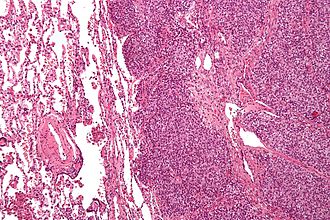

Lung metastasis (Ewing sarcoma). H&E stain. | |

Lung metastasis (ES) - intermed. mag. (WC/Nephron)